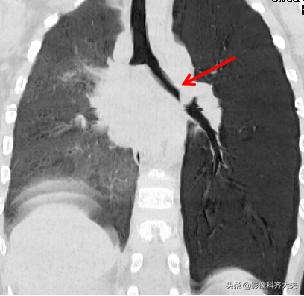

病例3、病史:患儿,两岁半。咳嗽近一个月,外院按支气管炎治疗半个月无好转。询问家属是否有吃东西呛咳病史,家属回忆一个月前还在好像吃过花生,瓜子,但不能完全确定。

图像显示在气管分叉的位置有一“瓜子”形异物的存在,尤其是冠状位显示更明显。